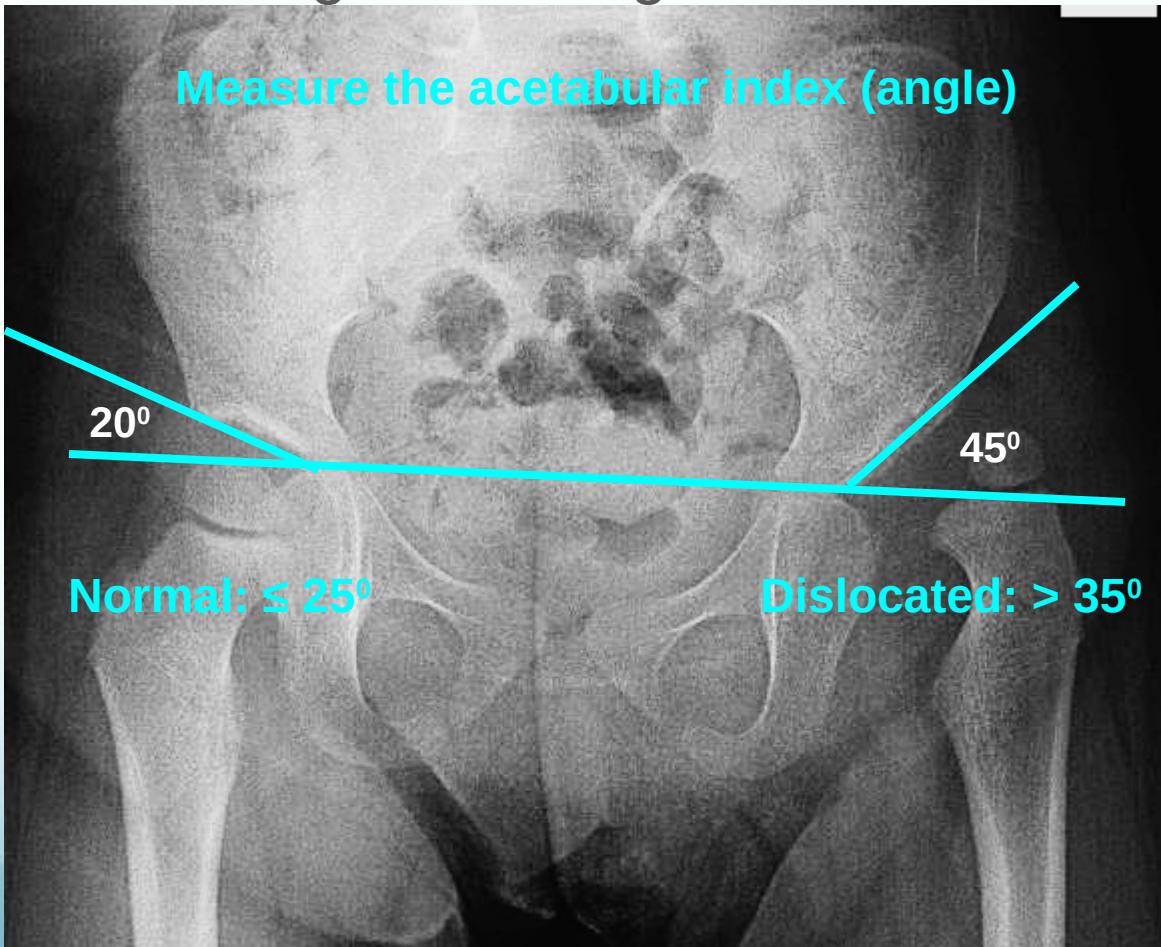

Acetabular angle (acetabular index):

- Normal: ≤ 25°

- Dislocated: > 35°